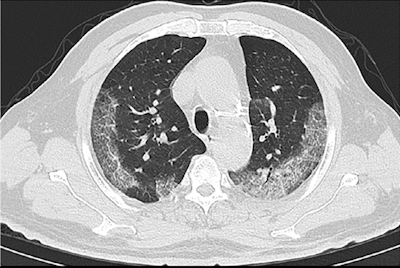

The researchers, led by Dr. Wenbin Ji from Affiliated Taizhou Hospital of Wenzhou Medical University, found that all but one of the patients' CT scans showed abnormal CT features associated with COVID-19, such as peripheral and subpleural ground-glass opacities in the lower lobes of both lungs.

To be precise, the sensitivity of diagnosing COVID-19 upon initial examination of the patients was 98% with chest CT, compared with 71% with RT-PCR (p < 0.001).